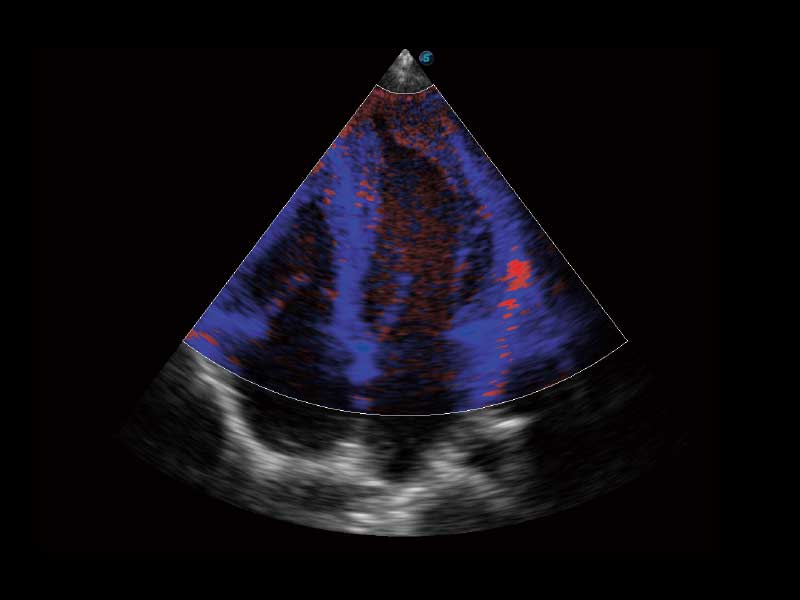

临床图